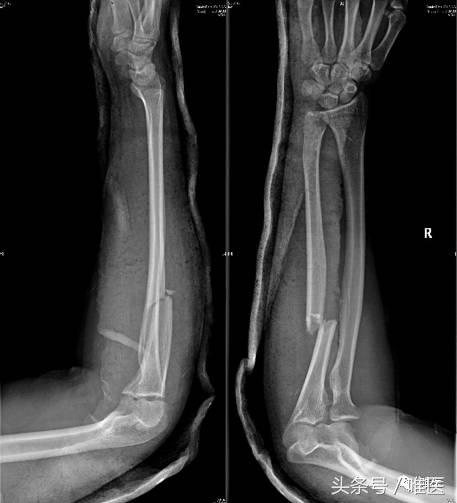

男性,19岁,自行车摔伤,右其前臂孟氏骨折。

▣ X线